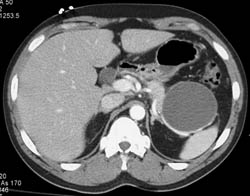

Diagnosis

Pseudocyst